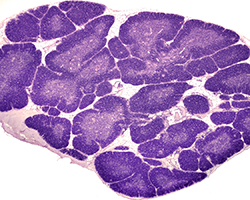

Órganos Linfoides

Órganos Linfoides

Ganglio linfático, bazo y timo.

(8 preparaciones) -